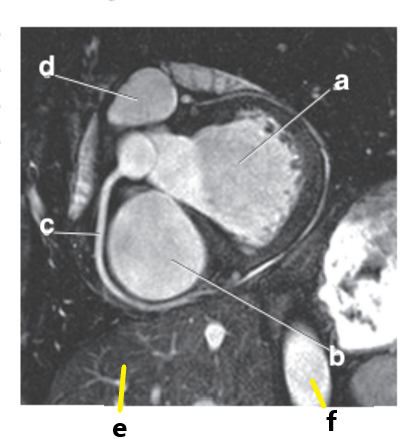

Which letter is the Pulmonary trunk ?

d

Which letter is the Descending aorta ?

f

Which letter is the superior vena cava ?

What is letter a ?

Left atrium

What is letter b ?

Left ventricle

What is letter c ?

What is letter d ?

Pulmonary trunk